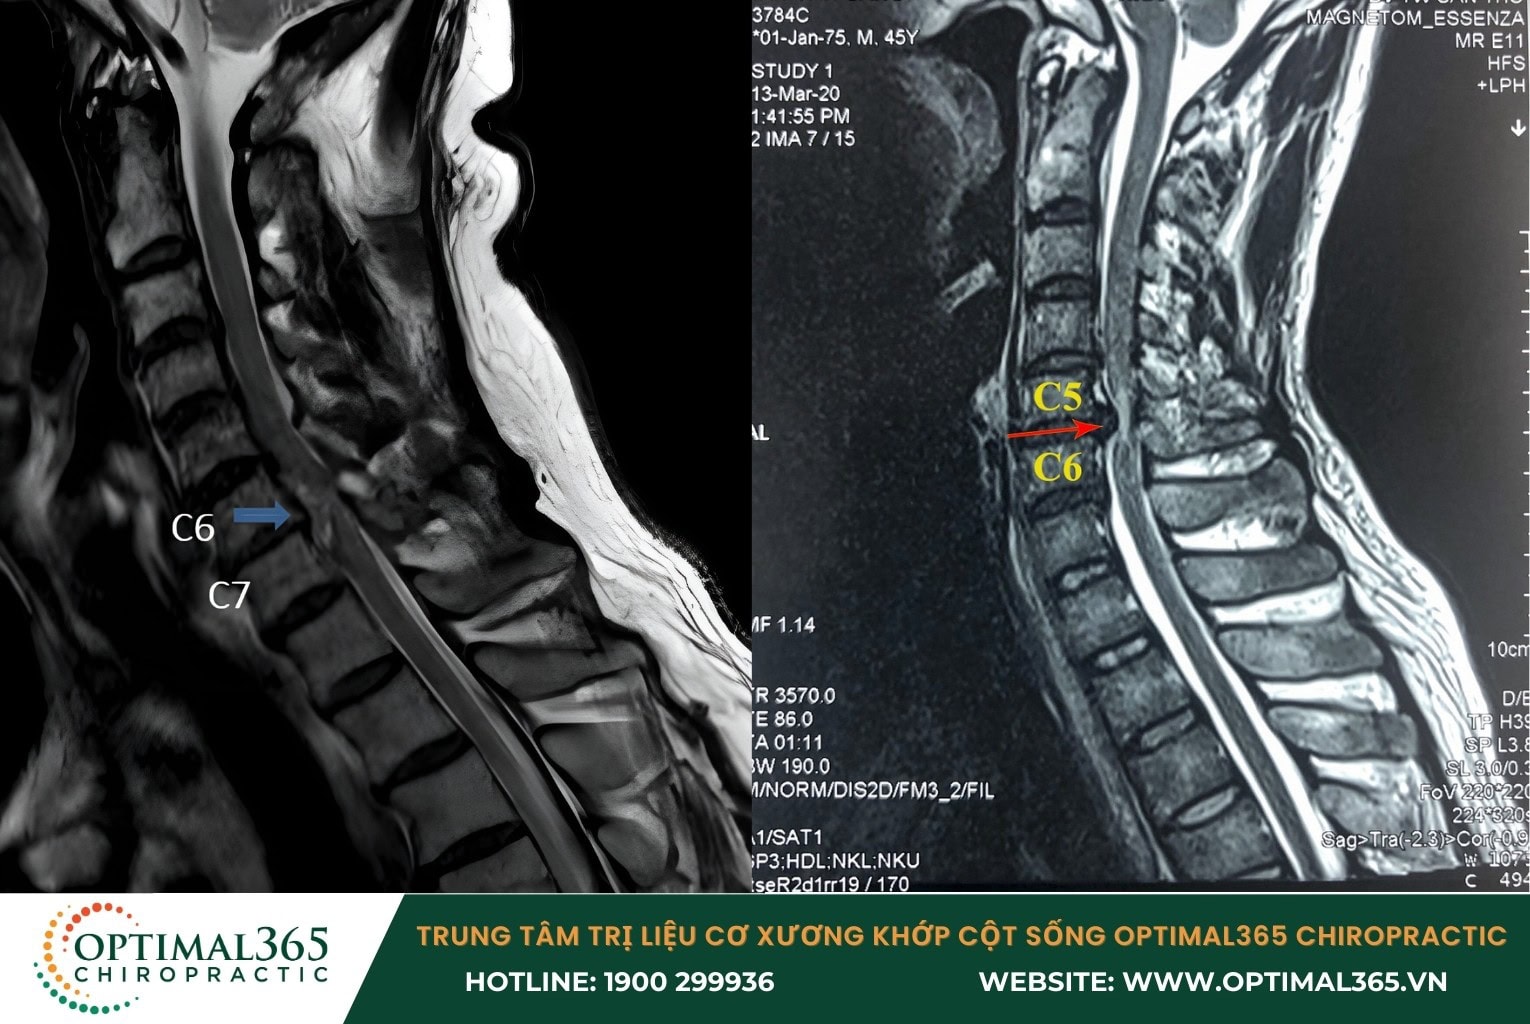

Dấu hiệu thoát vị đĩa đệm cột sống cổ cận lâm sàng

Trong các trường hợp cận lâm sàng, các triệu chứng thoát vị đĩa đệm cột sống cổ này thường được phát hiện qua chụp MRI với những biểu hiện như: Đĩa đệm thoát vị ra phía trước hoặc sau, khối nhân nhầy không ở vị trí bình thường, cùng với sự thay đổi cấu trúc cột sống và dấu hiệu chèn ép lên rễ dây thần kinh hoặc tủy sống.